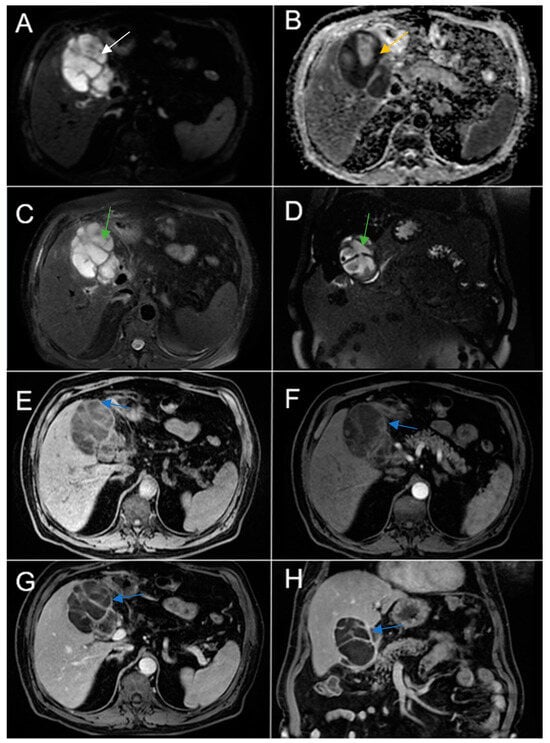

Therefore, clinical suspicion of gallbladder carcinoma was raised and an MRI cholangiography was performed (Figure 3). A laparoscopic cholecystectomy was performed and a subhepatic tumoral block with transvers colon invasion was identified. The patient was referred to the Oncology Department for further specialized treatment and follow-up.

Figure 3. Abdominal MRI sequences highlighting imaging features suggestive of gallbladder carcinoma. (A) Diffusion-weighted imaging (DWI B800) showing bright high signal intensity of the wall thickening of the gallbladder (white arrow). (B) On apparent diffusion coefficient (ADC) map, the wall thickening is dark (black arrow)—illustrating markedly diffusion restriction—which in correlation with increased levels of CEA and CA 19-9 is highly suggestive of gallbladder carcinoma. (C) Axial T2-weighted FIESTA showing asymmetric strongly inhomogeneous wall thickening involving the gallbladder (yellow arrow). (DF). Axial contrast-enhanced T1-weighted images showing heterogeneous enhancement of the wall thickening (green arrows).